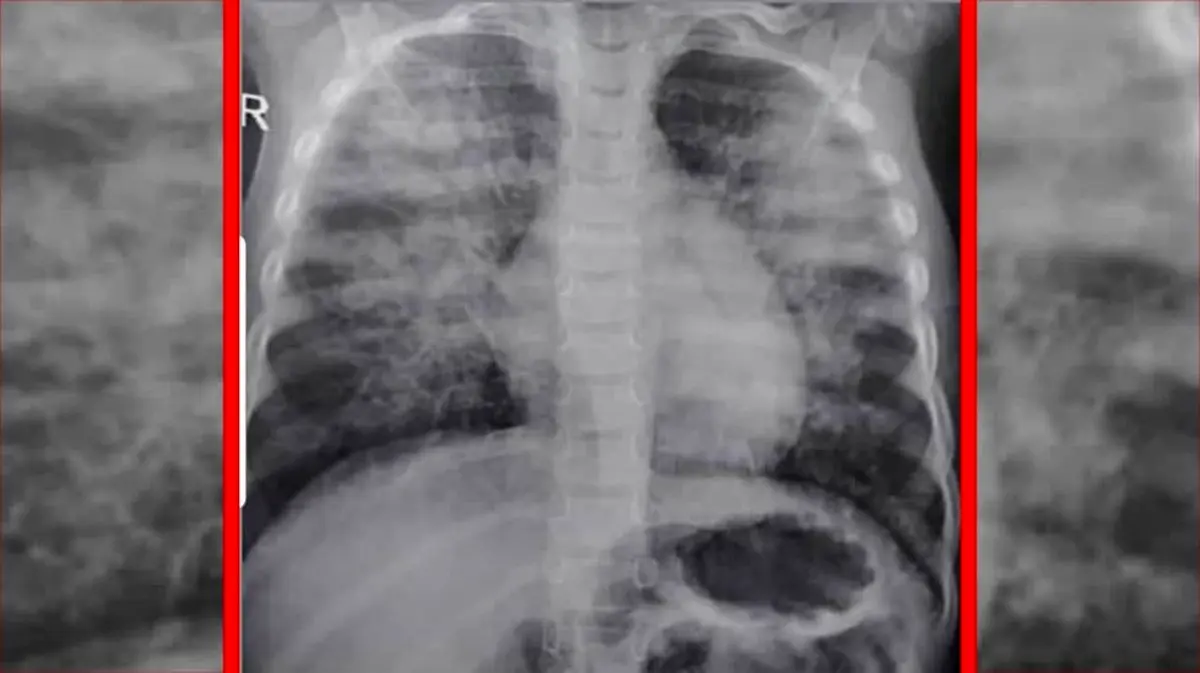

ریه بچه 3 ساله در خوزستان

دکتر هادی یزدانی، پزشک و نائب رئیس هیئت داوری حزب اتحاد ملت ایران اسلامی در توئیتر خود عکس ریه یک کودک 3 ساله را منتشر کرده و نوشت: این عکس را امشب یکی از دوستانم در اینستاگرام گذاشته بود. عکس ریه‌ی یک کودک ۳ ساله‌‌ اهل یکی از شهرهای خوزستان که دچار کووید_۱۹ شده و کمتر از ۳ ساعت پس از ورود به بیمارستان فوت می‌کند. ریه‌های درگیر کودک را ببینید و کمی بترسید؛ کرونا این روزها جوان و پیر نمی‌شناسد.آخرین قیمت های بازار ایران را اینجا کلیک کنید.